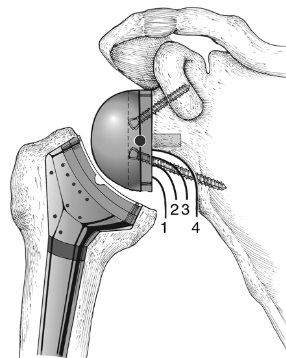

고관절 치환술(Total Hip Arthroplasty)

적응증: 고관절 치환술은 고관절 골관절염, 류마티스 관절염, 무혈성 괴사 또는 고관절 골절이 있는 개인에게 일반적으로 수행됩니다.

절차: 고관절 치환술 중 손상된 고관절의 볼-소켓 구성 요소를 인공 부품으로 교체합니다. 이 절차는 다양한 수술적 접근법을 사용하여 수행될 수 있습니다.

혜택: 고관절 치환술은 통증을 완화하고 고관절 기능을 회복하며 환자가 독립성과 이동성을 회복할 수 있도록 해줍니다.